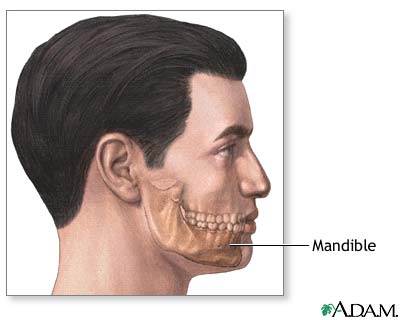

Chin augmentation is surgery to reshape or enhance the size of the chin. It may be done either by inserting an implant or by moving or reshaping the jaw bones.

Chin augmentation is mostly done to balance the appearance of the face by making the chin longer or bigger compared to the nose. The best candidates for chin augmentation are people with small or receding chins (microgenia), but who have a normal bite.